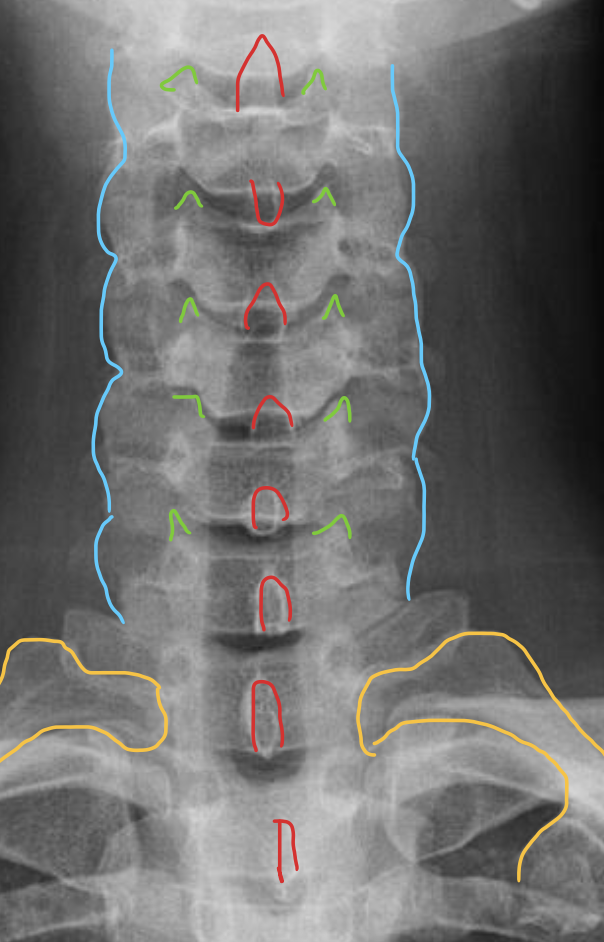

钩突

Uncinate process

关节柱 / 侧块

Articular pillars

棘突

Spinous process

T1

1ST Rib